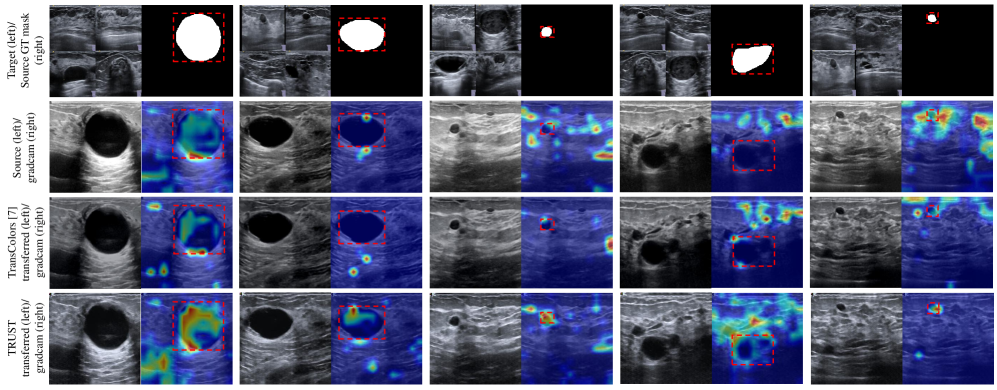

Refer to caption

Figure 3: GradCAM [16] comparison of style transfer methods, including Source without transfer (Source), TransColors [6], and our proposed TRUST. The GradCAM visualizations highlight the attention regions of a frozen downstream classifier on the BUSI\rightarrowUCLM transfer task. The source mask (top-right) delineates the ground-truth tumor region that the model should attend to for accurate classification, while the target images (top-left) serve as style references for the style transfer methods. Notably, the transferred source images (bottom-left) produced by TRUST exhibit more concentrated attention within the tumor region, thereby enhancing downstream classification performance.

Qualitative results. In Figure 3, we present visual comparisons and Grad-CAM [16] results on the test set, revealing several key observations. First, TRUST outperforms TransColors in capturing diverse styles within a specific target domain. Its outputs clearly reflect this strength, showing the closest resemblance to the target samples in color and brightness. Second, TRUST generates finer tissue details and clearer tumor boundaries, highlighting the advantage of using reliable information. Third, TRUST improves semantic cues for downstream classification, as shown by Grad-CAM maps that focus more precisely on tumors and their boundaries, indicating more effective attention to diagnostically relevant regions. Overall, TRUST achieves precise style transfer and task-focused attention, providing clear advantages over conventional approaches that treat all target information equally.